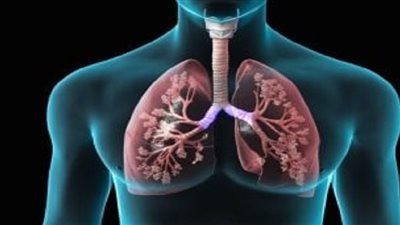

ما هي أعراض النفاخ الرئوي؟.. النفاخ الرئوي أو ما يسمى انتفاخ الرئة هو اضطراب تنفسي مزمن يؤدي إلى فقدان مرونة أنسجة الرئة وتلف الحويصلات الهوائية، مما يعوق التبادل الطبيعي للغازات ويؤدي إلى احتباس الهواء في الرئتين وصعوبة في التنفس، خاصة أثناء الجهد البدني، فهيا نتعرف خلال هذا التقرير على ما هي أعراض النفاخ الرئوي؟.

تشخيص النفاخ الرئوي

يعتمد تشخيص النفاخ الرئوي على الفحص السريري الدقيق إضافة إلى مجموعة من الفحوصات المتخصصة، ومن أبرزها:

- المعاينة الجسدية؛ فيلاحظ الطبيب تغيرات في طريقة التنفس مثل: الشهيق باستخدام عضلات إضافية، ضمور عضلات الكتف، وصفير في الصدر.

- مع تحليل غازات الدم الشرياني؛ لقياس مستويات الأكسجين وثاني أكسيد الكربون.

- وتصوير الصدر بالأشعة السينية أو المقطعية؛ للكشف عن فرط الانتفاخ أو وجود فقاعات هوائية